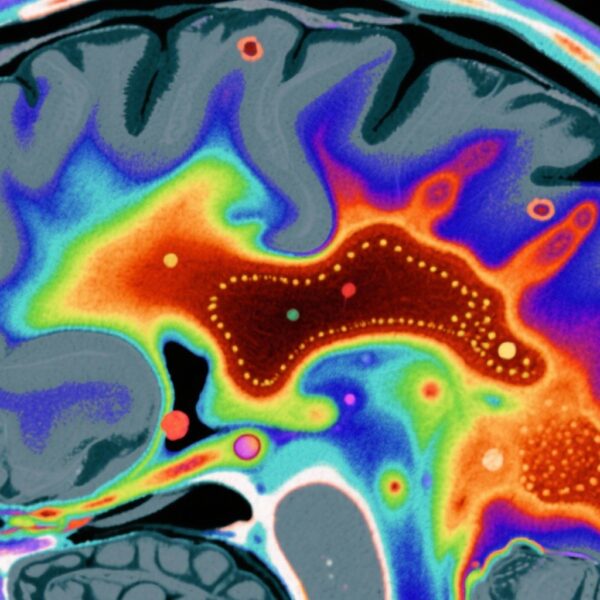

統合失調症スペクトラム障害(SSD)は、統合失調症、統合失調感情障害、一過性統合失調症を含む重度の精神障害であり、幻覚や妄想などの精神病症状が特徴です。これらの障害は、世界的に機能障害、病態、死亡率に大きな影響を与えています。米国では、SSDは約1%の生涯有病率を持つ重要な公衆衛生課題となっています。特に、疫学研究は、非ヒスパニック黒人と複数人種の人口が非ヒスパニック白人に比べてSSDの有病率が高いことを一貫して示しています。

本研究では、非高齢米国人成人(N=4,764)を対象とした全国代表的な世帯サンプルからデータを使用しました。参加者は、過去1年間および生涯のSSD(統合失調症、統合失調感情障害、一過性統合失調症)の有病率と陽性精神病症状の識別のために、DSM-5用構造化臨床面接(SCID-5)を受けました。